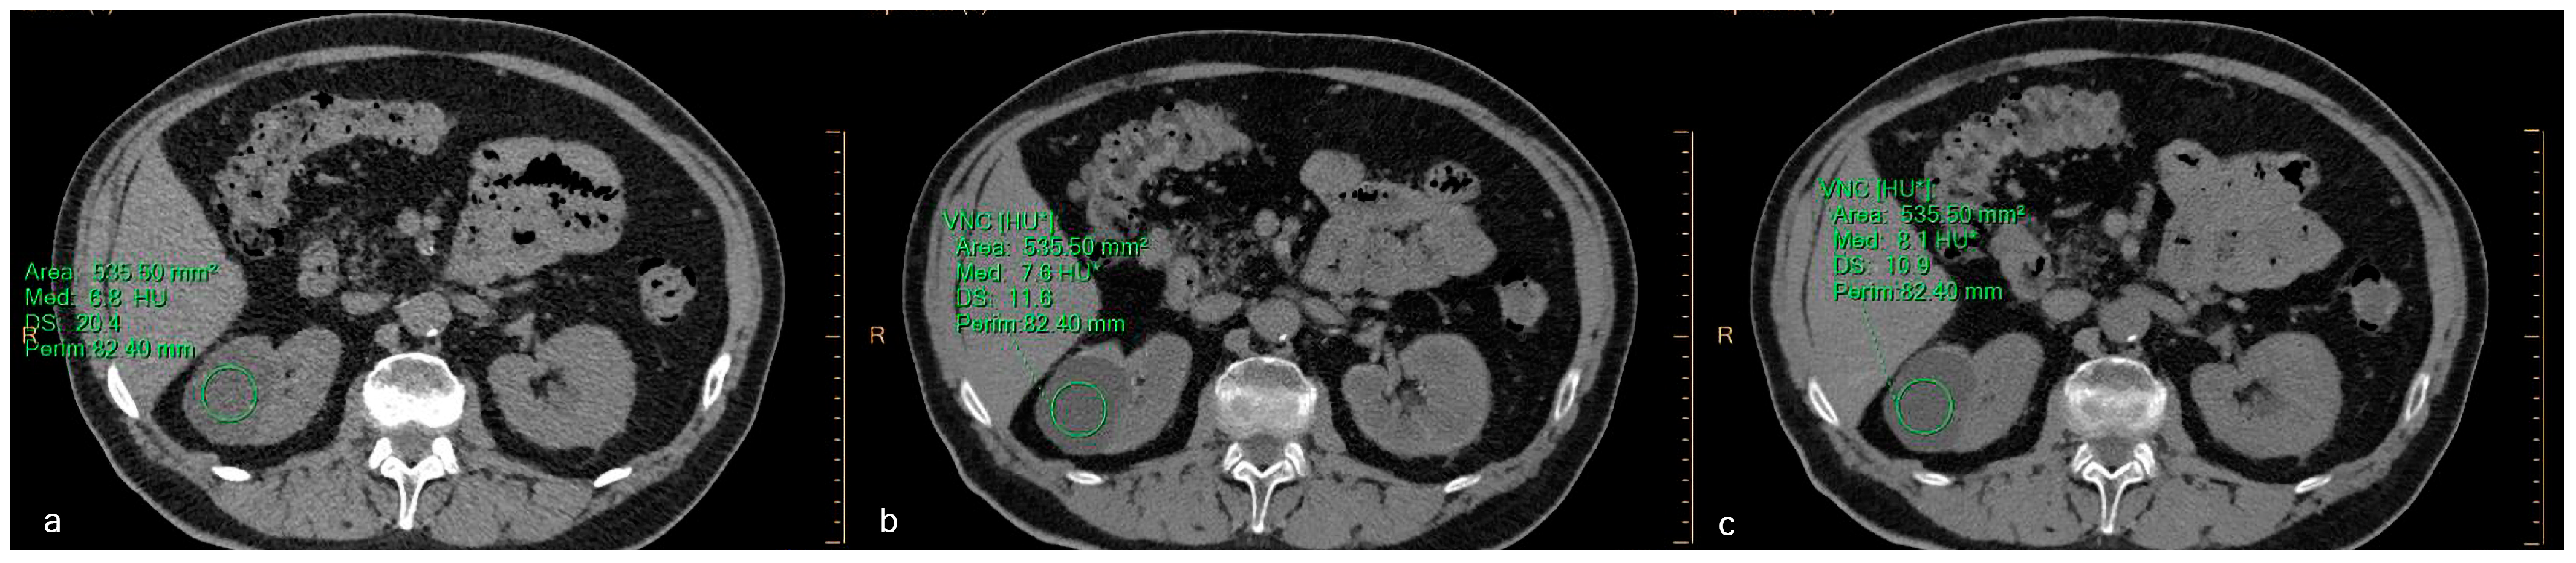

2.4. Objective Image Evaluation

3.2. Quantitative Assessment

| Type of Lesion | Phase | Mean Value (HU) | SD |

|---|---|---|---|

| All lesions | TNC | 17.6 | 16.5 |

| VNCcort | 15.7 | 13.2 | |

| VNCneph | 15.6 | 12.7 | |

| Simple Cysts | TNC | 10.7 | 15.6 |

| VNCcort | 7.8 | 12.2 | |

| VNCneph | 7.5 | 11.9 | |

| Complex Cysts | TNC | 15.3 | 18.6 |

| VNCcort | 12.7 | 13.6 | |

| VNCneph | 13.1 | 14.4 | |

| Renal Masses | TNC | 34.3 | 16.9 |

| VNCcort | 34.1 | 15.1 | |

| VNCneph | 33.9 | 13.4 |